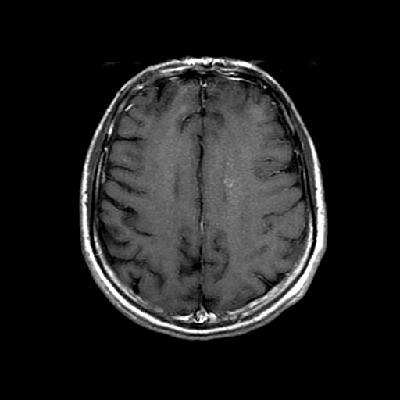

Neurologic and mental examination showed intact immediate memory but inability to recall 3 objects in 5 minutes. He was not oriented to time or space or situation but oriented to person. His remote memory was intact. There was left superior quadrantonopsia but no focal motor or sensory deficits. FLAIR images on MRI showed a lesion in the left mesial temporal lobe (Panel 1). This lesion had increased T2 signal but without enhancement on T1 images. This lesion also had mass-effect and edema within that region. On FLAIR images, there were some small foci of abnormal signal in the white matter of the right parietal lobe (Panel 2) but these foci did not enhance (Panel 3). There is a vague, poorly demarcated, triangular shaped periventricular signal abnormality in the left parietal lobe (Panel 2) but this area did not enhance (Panel 3). On another image (obtained higher to Panel 2 and 3), however, there is a small cluster of enhancing spotty signal in the white matter of the left parietal lobe (Panel 4) and the largest focus is about 0.4 cm in diameter. There were areas with features of encephalomalacia in his right mesial temporal lobe that would be explained by his history of prior infarct.

1. FLAIR |

2. FLAIR |

3. T1+Contrast |

4. T1+Contrast |